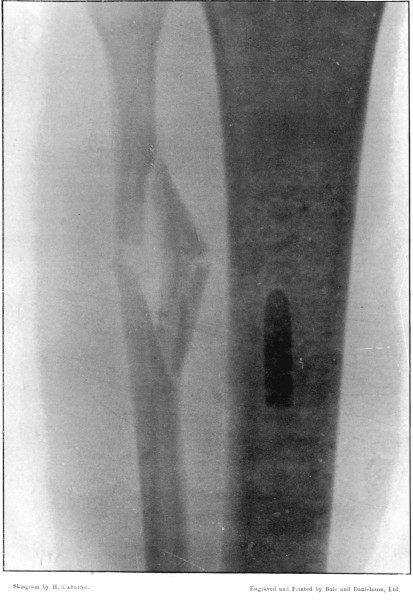

10. Wedge-shaped Fracture of the Radius192

11. Fracture of the Metacarpus, showing Fragmentation of the Bullet194

24. The same Fracture, Lateral View 220

25. Vickers-Maxim Fracture of the Humerus 482